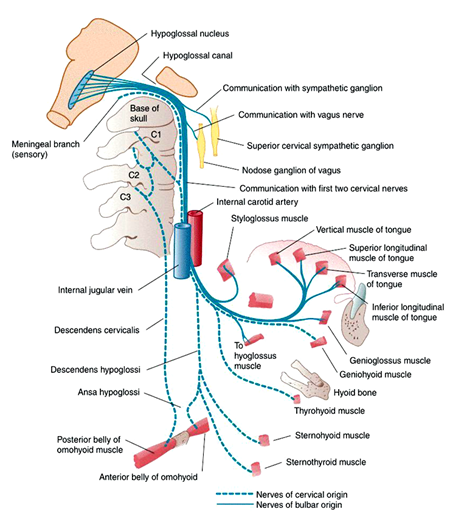

The Hypoglossal Nerve (CN XII) – Course – Motor – TeachMeAnatomy

Hypoglossal Nerve (CN-XII)

Hypoglossal Nerve (CN-XII)

Hypoglossal Nerve (CN-XII)

Hypoglossal Nerve (CN-XII)